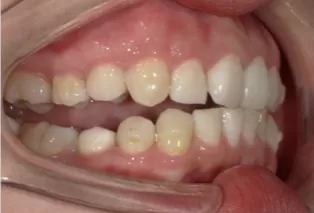

Intraoral photos